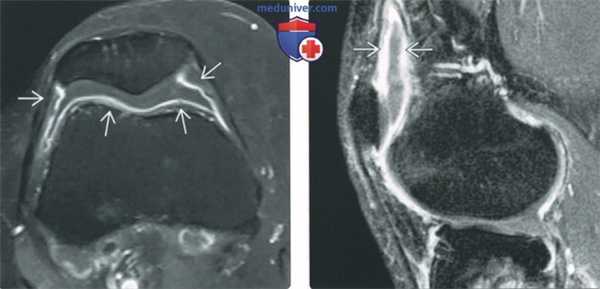

(Слева) Аксиальная Т1 С+ FS МРТ коленного сустава: определяется нормальная экскреция синовиальной оболочкой введенного внутривенно гадолиния, формирующего тонкое кольцо усиления.

(Справа) Сагиттальная Т1 С+ FS МРТ в более отсроченную фазу после инъекции, чем на предыдущем изображении: визуализируется небольшое утолщение синовиальной оболочки. Это отражает распространение контраста за пределы синовиальной оболочки и не должно быть ошибочно принято за синовит. Для получения непрямой артрограммы сустав должен быть разработан с целью обеспечения однородного распределения контраста в суставе.

б) Непрямая артрография. Контрастные препараты с гадолинием, введенные внутривенно, экскретируются синовиальной оболочкой. Контрастное вещество диффузно распространяется в суставной полости, подчеркивая хрящевые структуры и связки. Этот феномен используется для получения «непрямой артрограммы».

В ранние фазы после внутривенного введения контрастного вещества контраст находится рядом с синовиальной оболочкой. Такое расположение контраста создает впечатление утолщения синовии. Для получения его однородного распространения в суставе визуализация откладывается на 20-30 минут после внутривенного введения контрастного вещества, а сустав перед обследованием пациента разрабатывается.